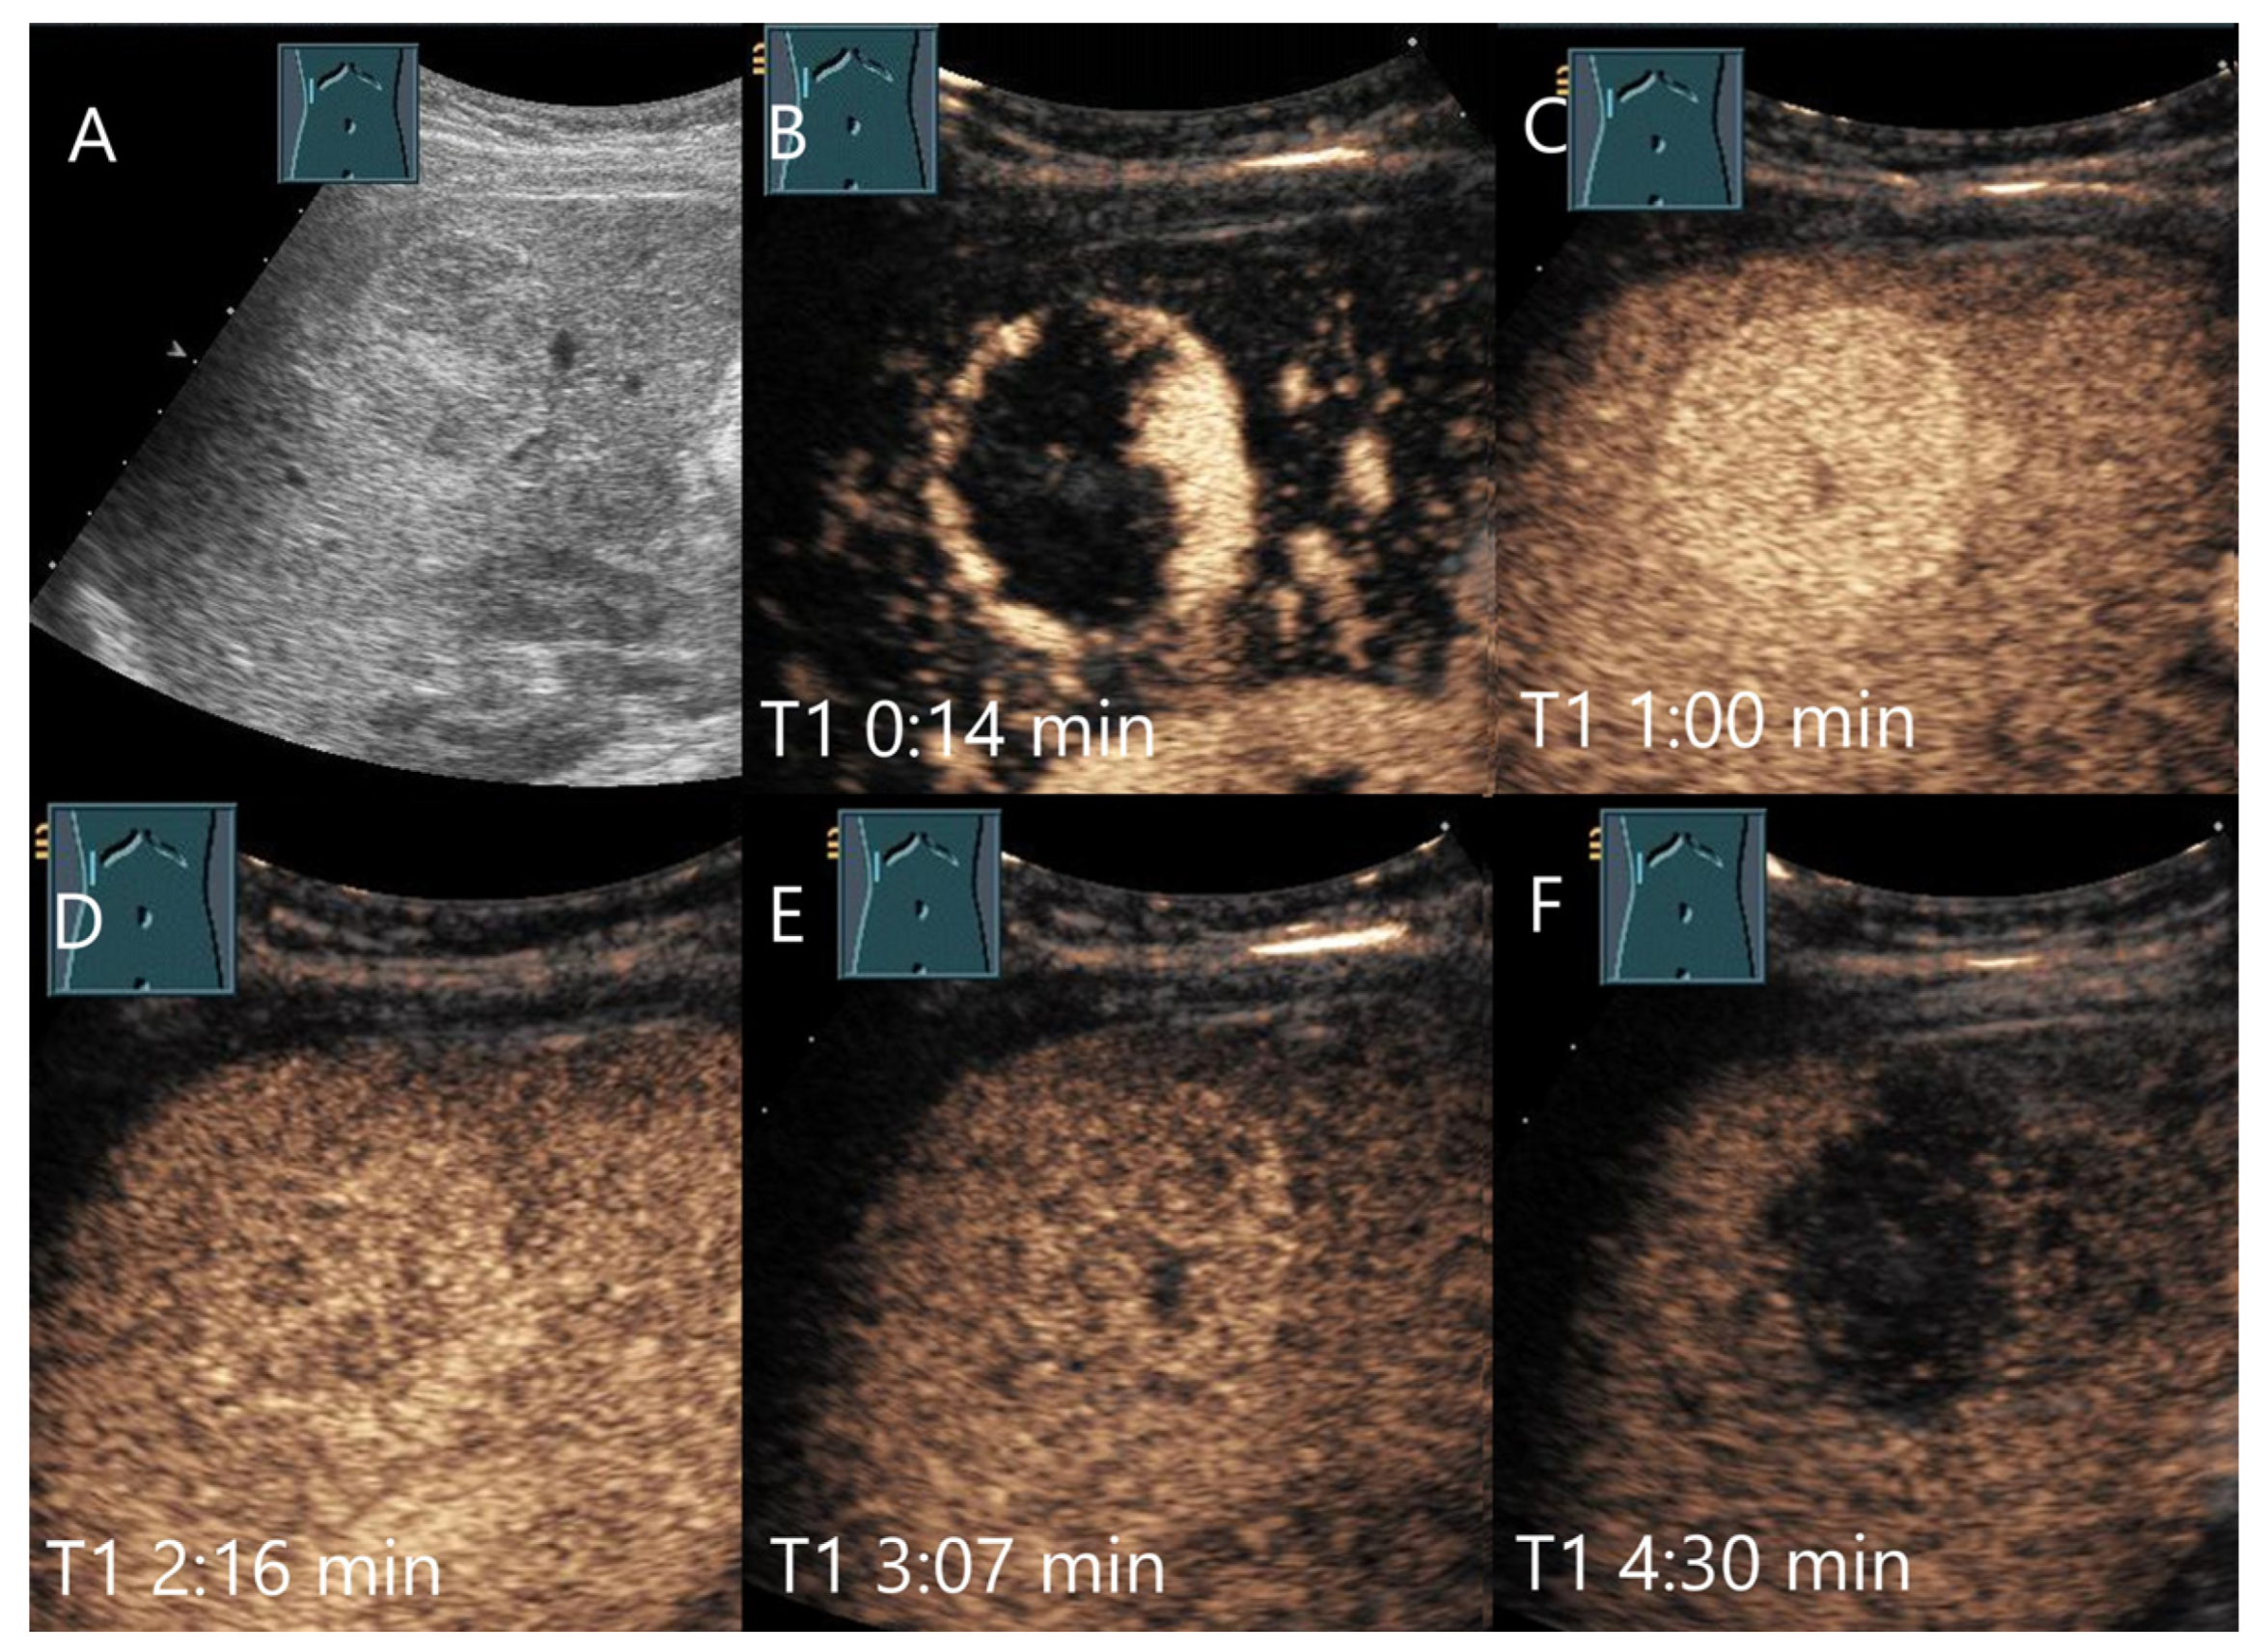

Figure 3.

Cavernous hemangioma. Female patient. Incidental finding of a 40 × 32 mm heterogeneous hypoechoic FLL (A). The CEUS shows arterial marginal hyperenhancement after 14 s (B) and homogeneous AP hyperenhancement after 1:00 min (C). Decreasing heterogeneous hyperenhancement after 2:16 min (D) and 3:07 min (E). After 4:30 min (F), there is a clear hypoenhancement. Clinical ultrasound revealed the diagnosis of a hemangioma. Histologically, a cavernous hemangioma was confirmed.